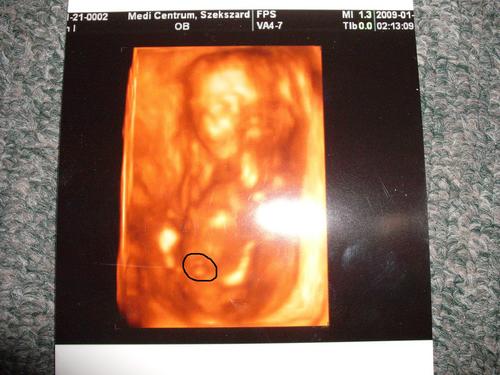

Bébikénk:

Kép

Tök rossz a minősége,de nincs szkennerünk,fényképezővel pedig ez volt a max,amit ki tudtam hozni :oops: :oops: